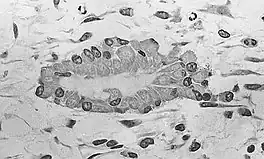

Osteoblasts (purple) rimming a bony spicule (pink - on diagonal of image). In this routinely fixed and decalcified (bone mineral removed) tissue, the osteoblasts have retracted and are separated from each other and from their underlying matrix. In living bone, the cells are linked by tight junctions and gap junctions, and integrated with underlying osteocytes and matrix H&E stain.

Morphology and histological staining

Hematoxylin and eosin staining (H&E) shows that the cytoplasm of active osteoblasts is slightly basophilic due to the substantial presence of rough endoplasmic reticulum. The active osteoblast produces substantial collagen type I. About 10% of the bone matrix is collagen with the balance mineral.[29] The osteoblast's nucleus is spherical and large. An active osteoblast is characterized morphologically by a prominent Golgi apparatus that appears histologically as a clear zone adjacent to the nucleus. The products of the cell are mostly for transport into the osteoid, the non-mineralized matrix. Active osteoblasts can be labeled by antibodies to Type-I collagen, or using naphthol phosphate and the diazonium dye fast blue to demonstrate alkaline phosphatase enzyme activity directly.